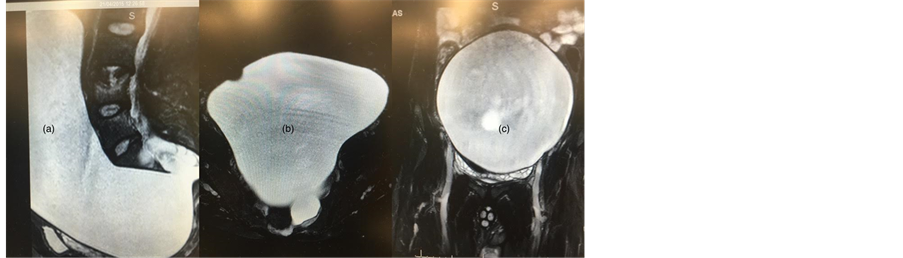

CT and MRI of the abdomen/spine were performed which showed a large anterior sacral meningocele occupying most of the pelvic and abdominal cavity and displacing their respective contents (Figure 1). The meningocele originated from the left anterolateral aspect of sacrum (S2 and S3) with no obvious neural structures passing through the defect on imaging.

Figure 1. MRI abdomen showing large anterior sacral meningocele in sagittal (a), axial (b) and cornoal (c) orientation.